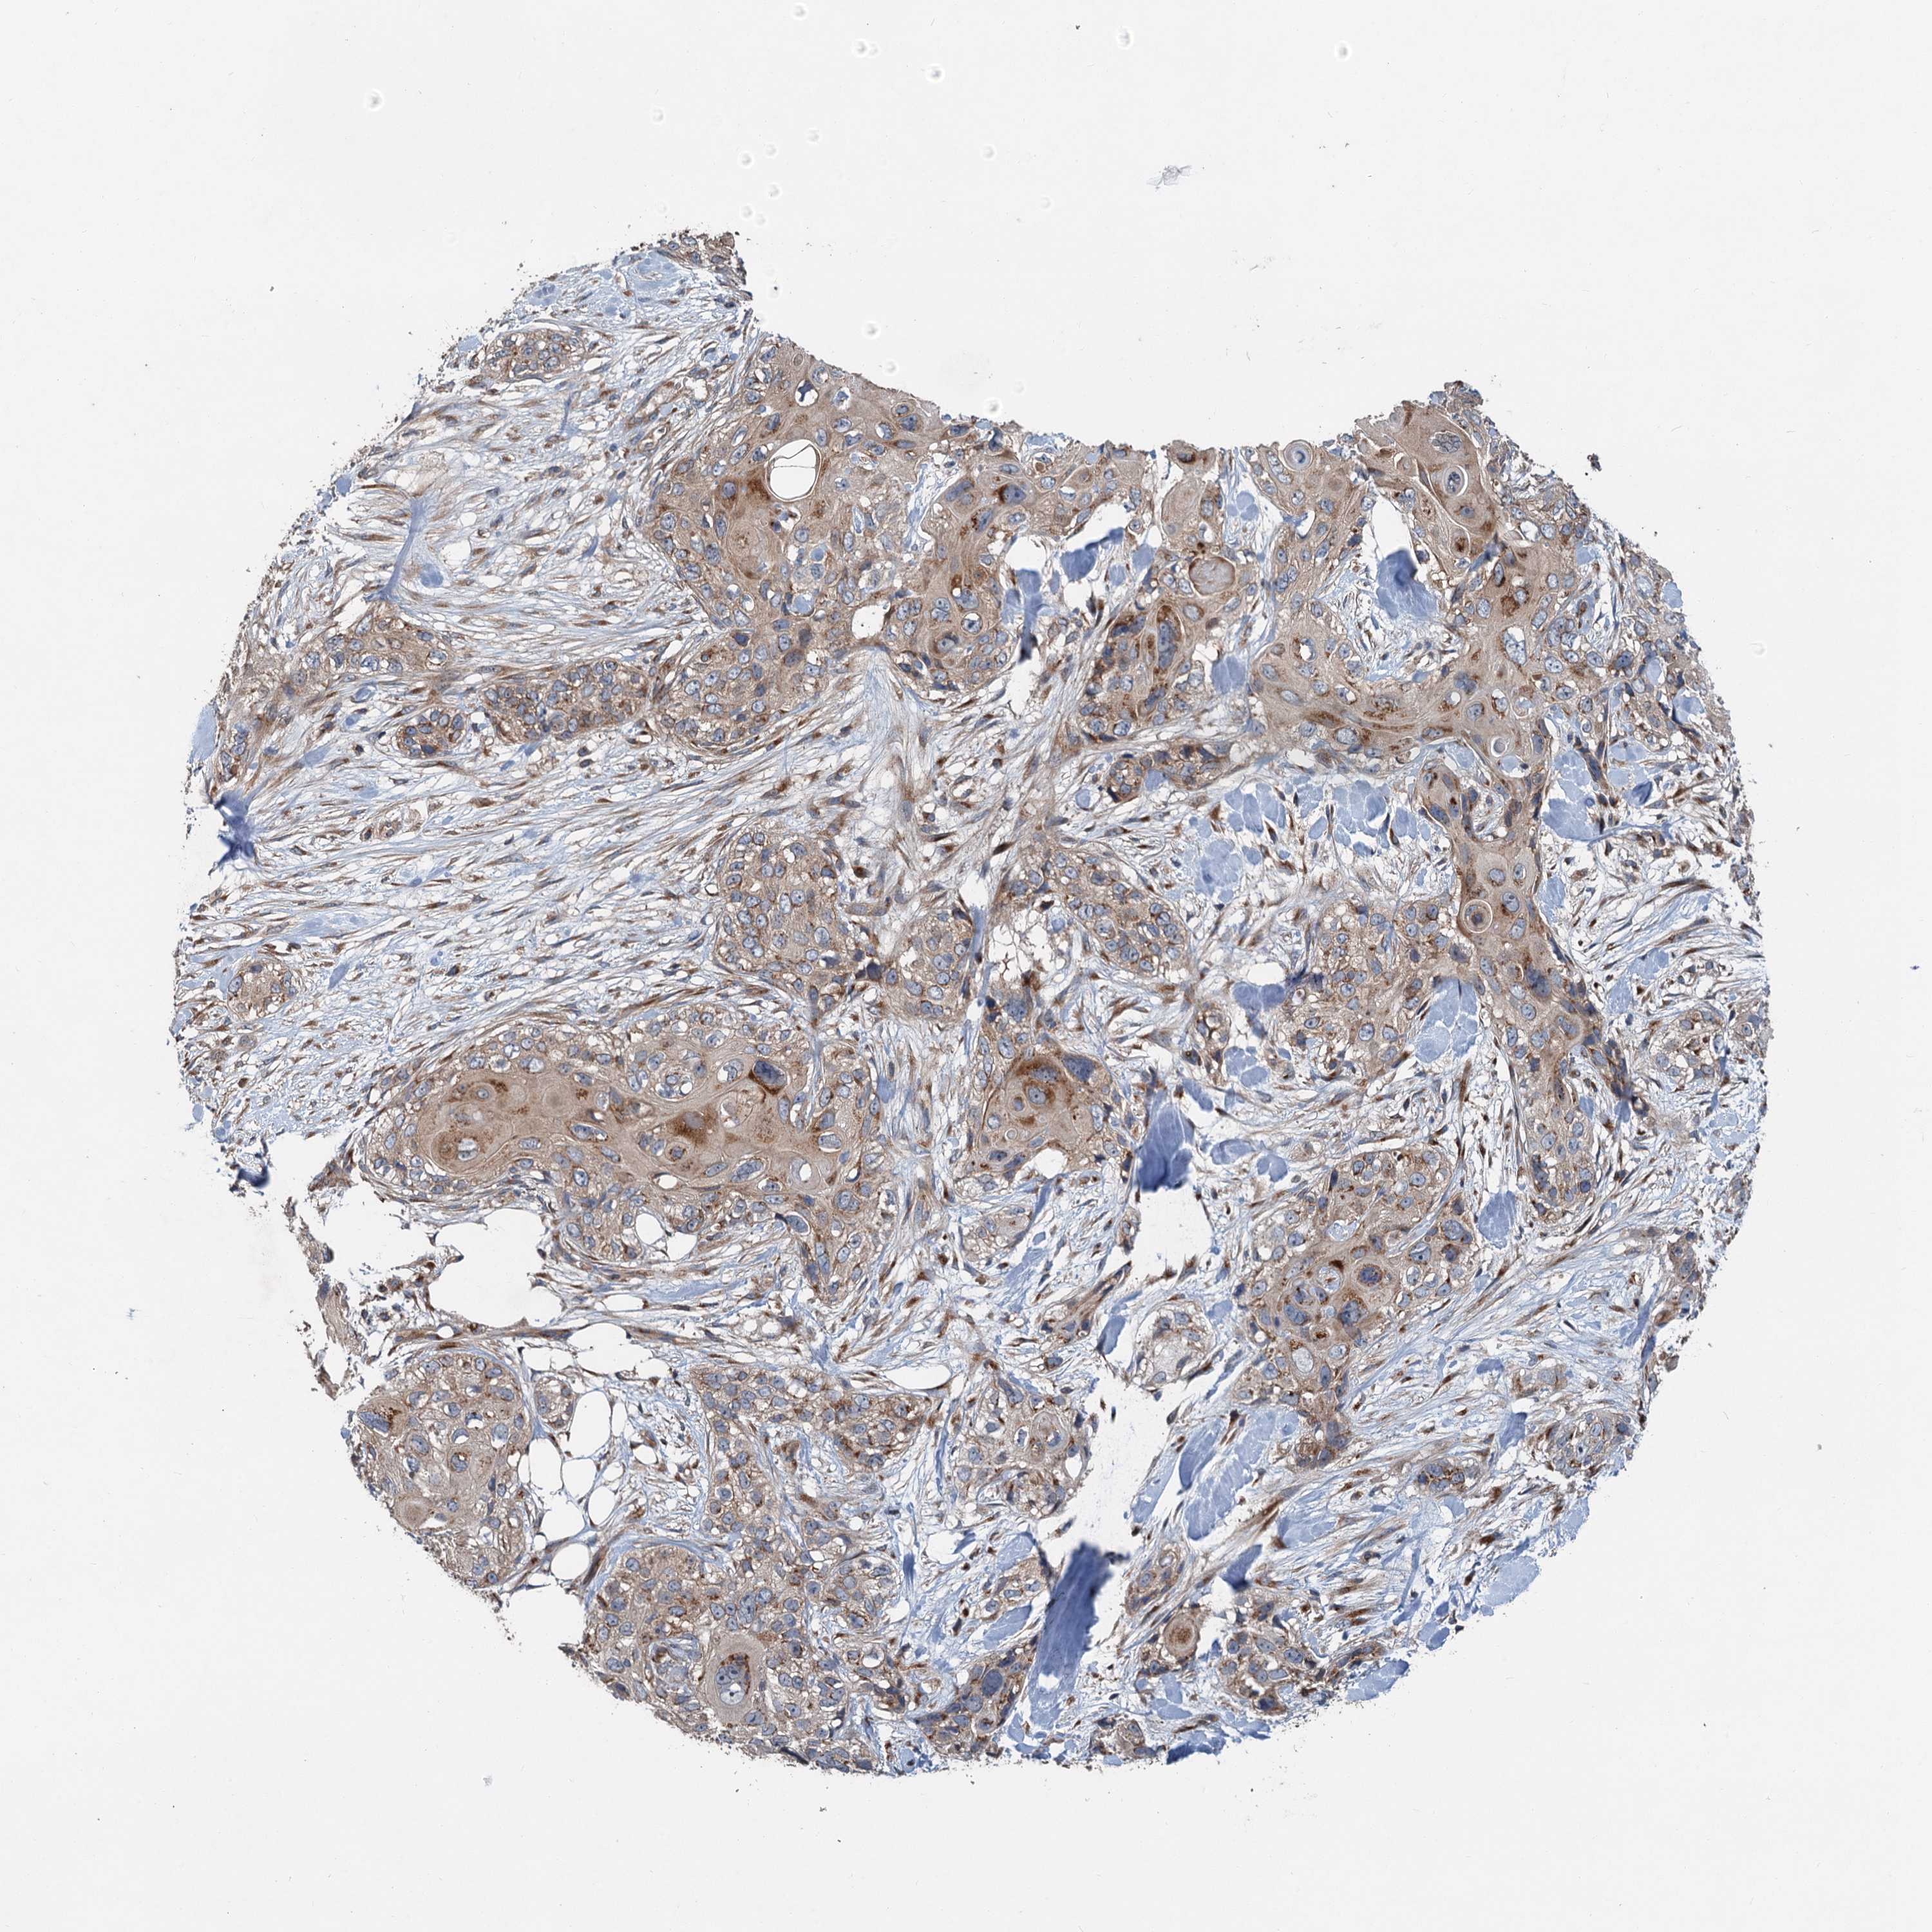

SKIN CANCER - Protein expressioni

A mouse-over function shows sample information and annotation data. Click on an image to view it in a full screen mode. Samples can be filtered based on level of antibody staining by selecting one or several of the following categories: high, medium, low and not detected. The assay and annotation is described here.

Antibody stainingi

Antibody staining in the annotated cell types in the current human tissue is reported as not detected, low, medium, or high, based on conventional immunohistochemistry profiling in selected tissues. This score is based on the combination of the staining intensity and fraction of stained cells.

Each image is clickable and will lead to virtual microscopy that enables deeper exploration of all samples and also displays staining intensity scores, fraction scores and subcellular localization as well as patient and tissue information for each sample.

Antibody HPA040353

Staining

High

Medium

Low

Not detected

Intensity

Strong

Moderate

Weak

Negative

Quantity

>75%

75%-25%

<25%

None

Location

Nuclear

Cytoplasmic/membranous

Cytoplasmic/membranous,nuclear

Basal cell carcinoma

Squamous cell carcinoma, NOS

Squamous cell carcinoma, metastatic, NOS